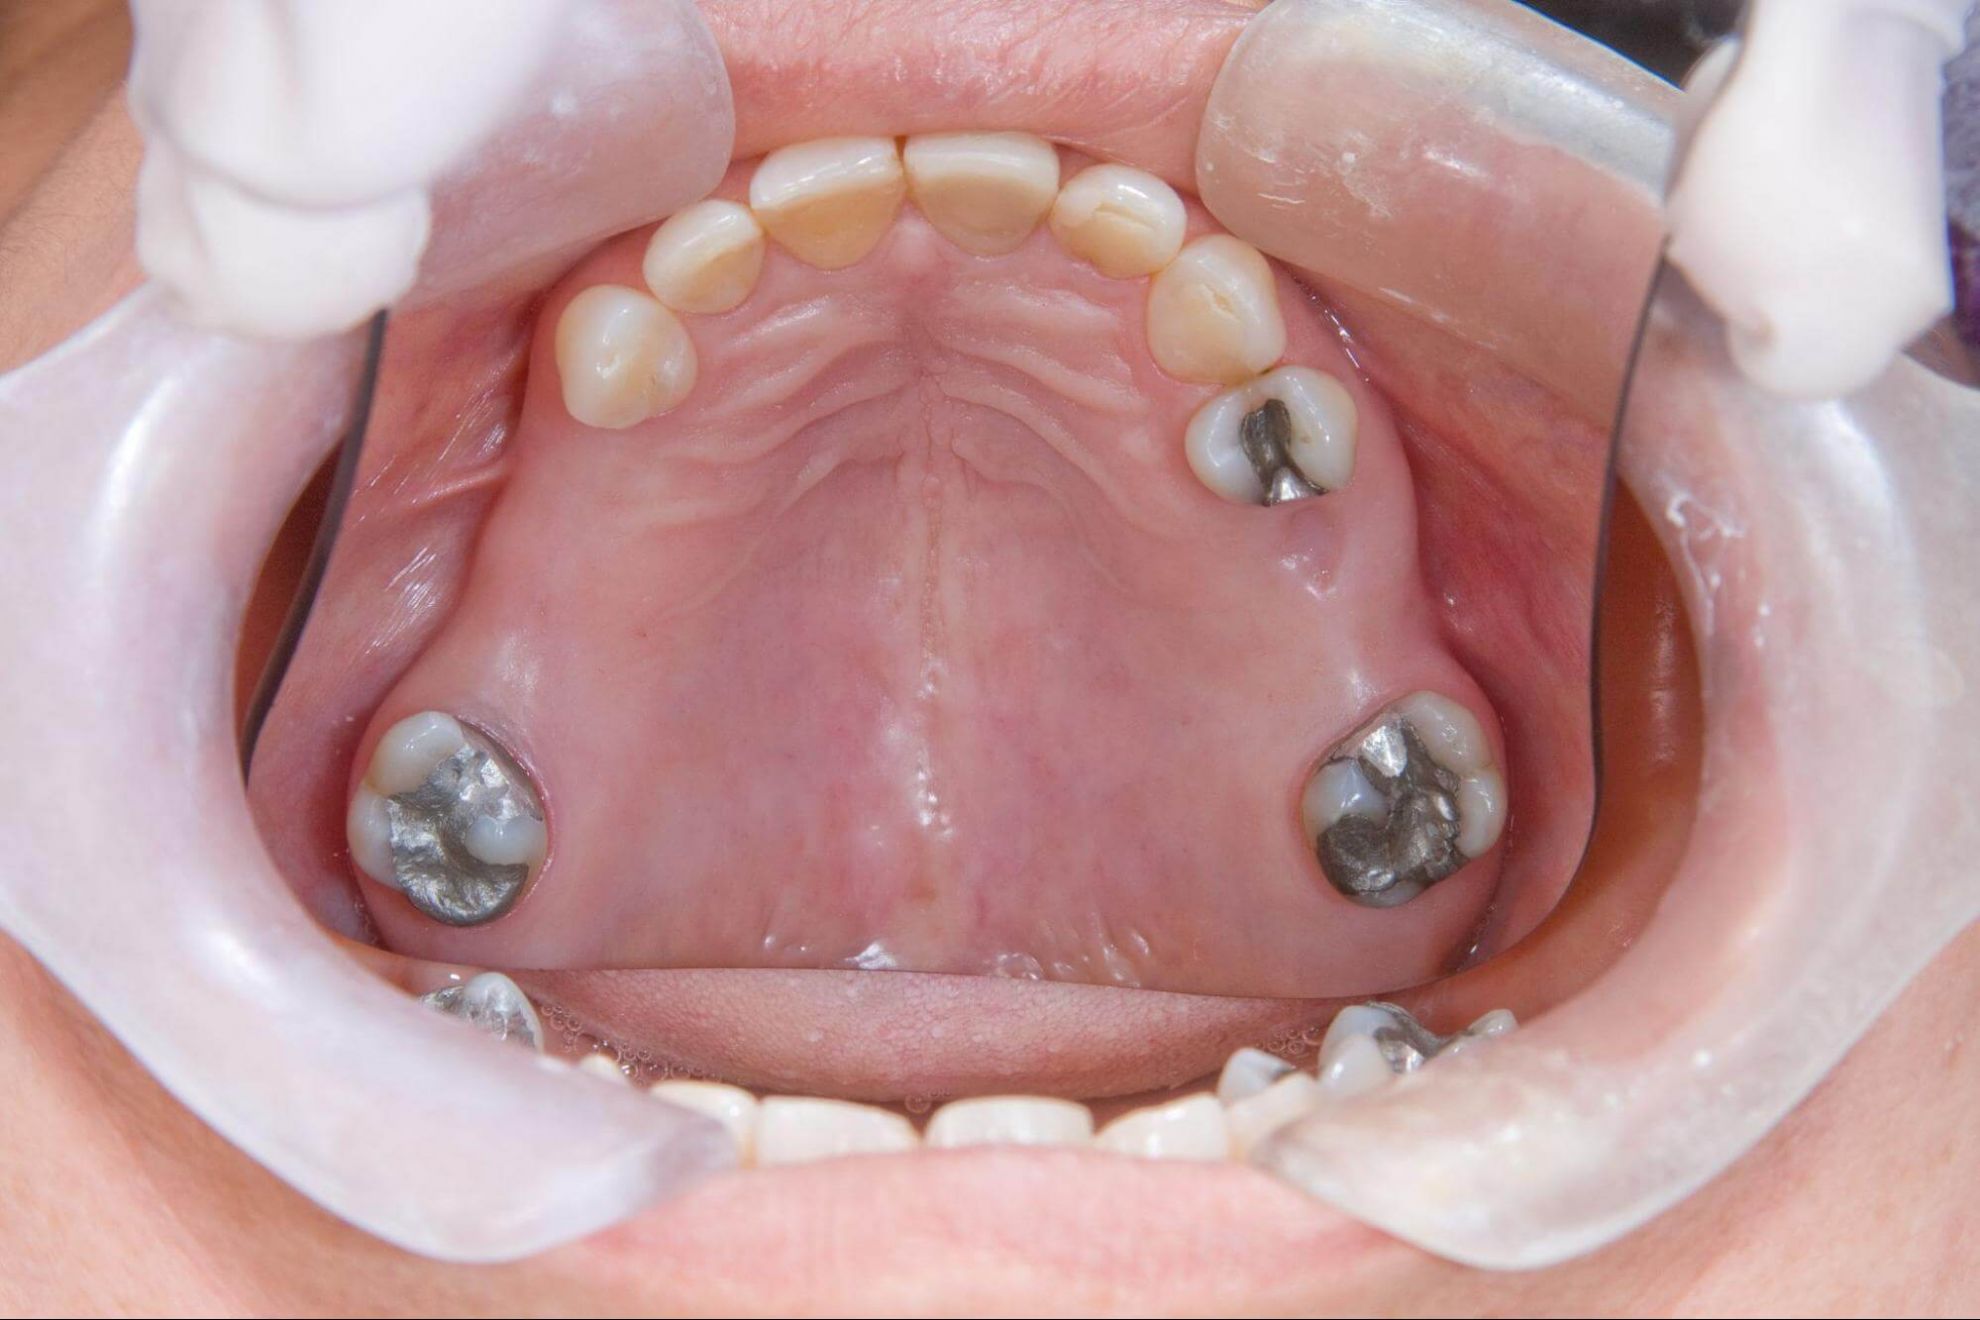

當牙齒長期受到蛀蝕、牙周病或外傷影響,可能會陸續鬆動、缺損,讓原本穩定的咬合被打亂。這些變化一開始或許不明顯,有些人便會選擇忽略,但隨著時間推進,骨頭開始流失、牙齒的支撐力也越來越弱,逐漸侵蝕口腔的健康,最終導致缺牙問題越來越嚴重。

而「全口重建」正是針對這樣的狀況所設計的治療方式,它的核心並不是單純補牙或植牙,而是透過 X 光與 3D 斷層影像檢查牙周健康、骨頭密度與咬合位置,評估整個口腔的受力與排列,再一步步重建出健康、穩定的咬合結構,評估哪些牙齒能保留、哪些需要重建。